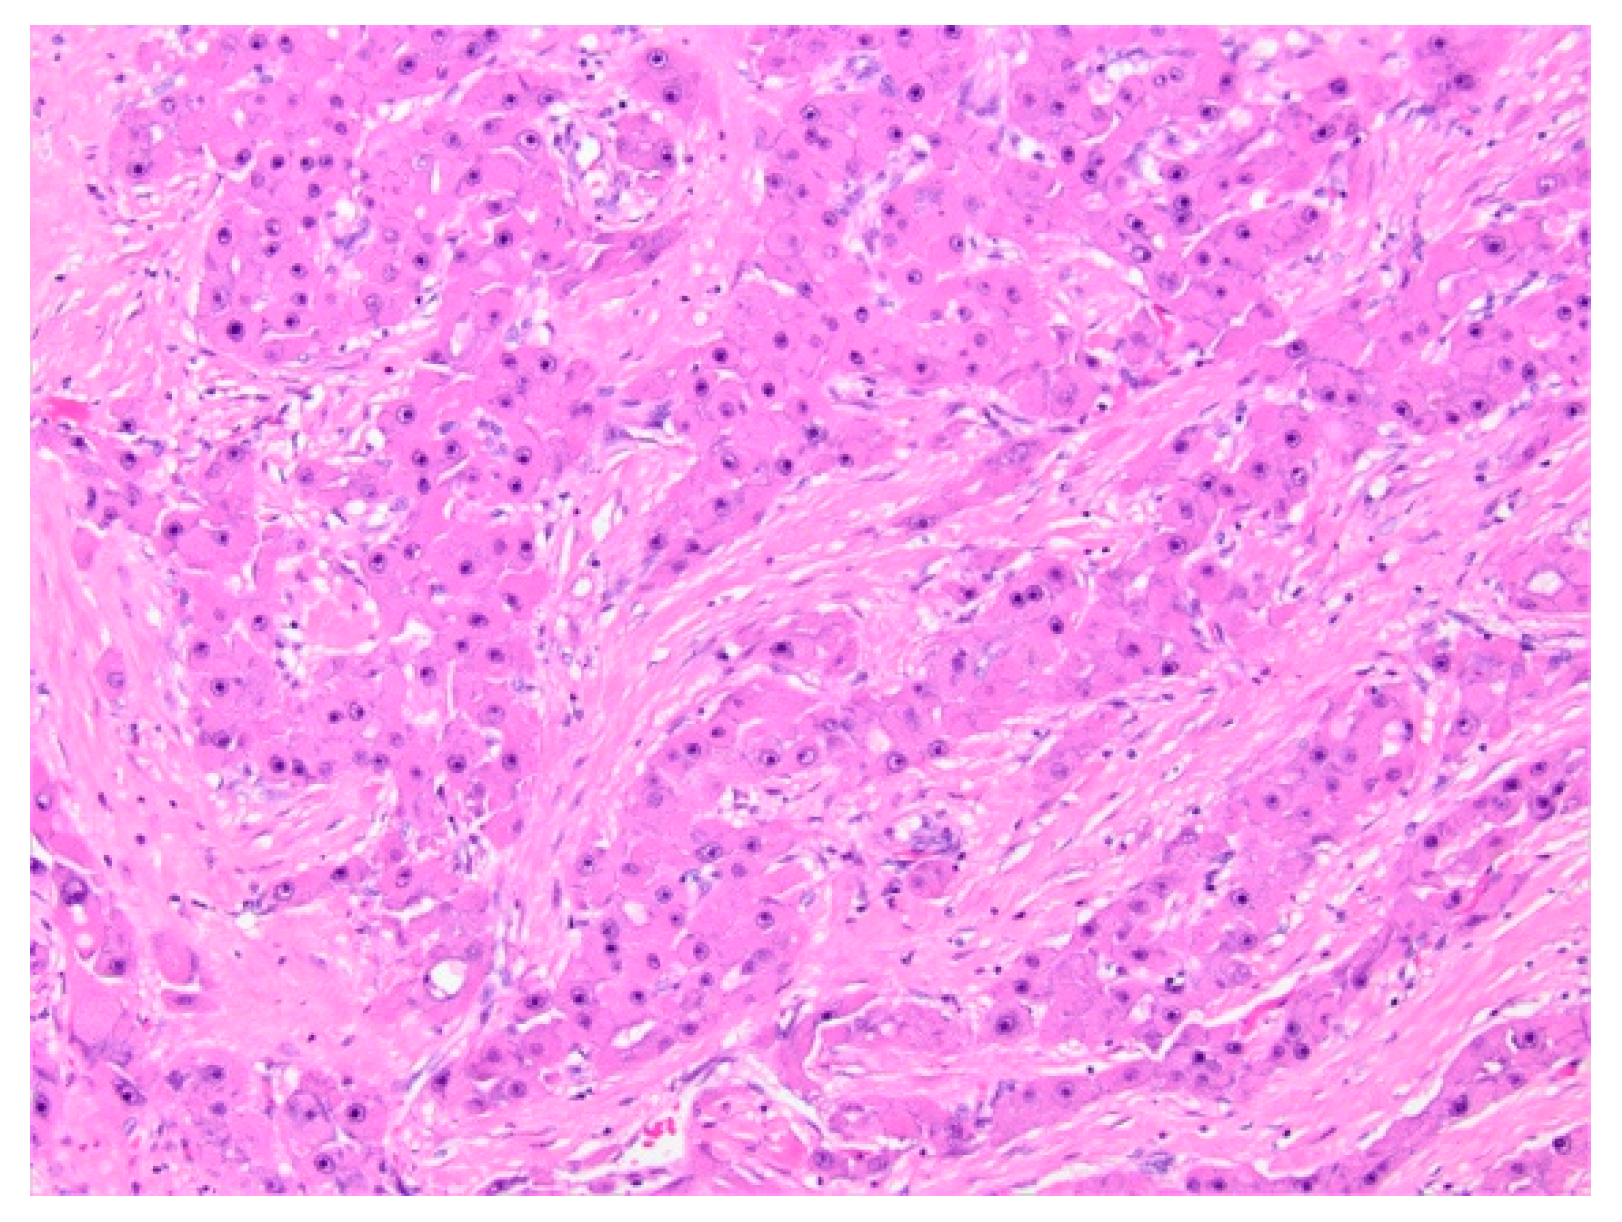

5.1.5. Histopathology and Immunohistochemistry